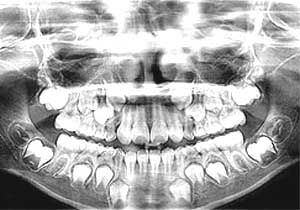

Panoramic x-ray

Dental x-rays are special pictures taken of the insides of the teeth so that the dentist and hygienist may see if the person has cavities between the teeth. It is very important to get these pictures taken regularly because the dentist cannot see the sides of the teeth that touch. If a cavity is between the teeth and an x-ray picture is not taken, the dentist will not know if the cavity is there and cannot treat the cavity and stop it from growing larger. If the cavity is left to grow, it can become very painful.